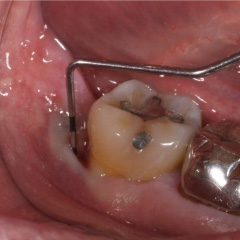

| 歯周病が進行したケースでは盲目下でポケット内の歯石を確実に除去するには限界があります。 | 局所麻酔をした後、歯茎を切開し、明視下にて歯根面の歯石や炎症組織を取り除き、歯周ポケットの除去をおこないました。 |

| 深い虫歯のケースでは、切除療法を行い虫歯を取り除き、健全な歯質を歯肉の上に出し、歯肉の盛り上がりを数ヶ月待ってから歯型をとります。 |

| 一見分りませんが、かなり歯周病が進行していました。歯周ポケットの改善や歯槽骨を平坦にして清掃しやすい環境を整えます。数ヶ月、歯肉の盛り上がりを待ってから適合の良いクラウンを被せます。 | ||